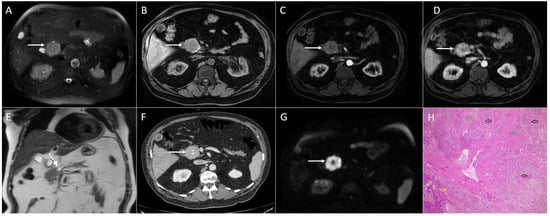

3.1. Neuroendocrine Tumors

3.3. Intrapancreatic Accessory Spleen